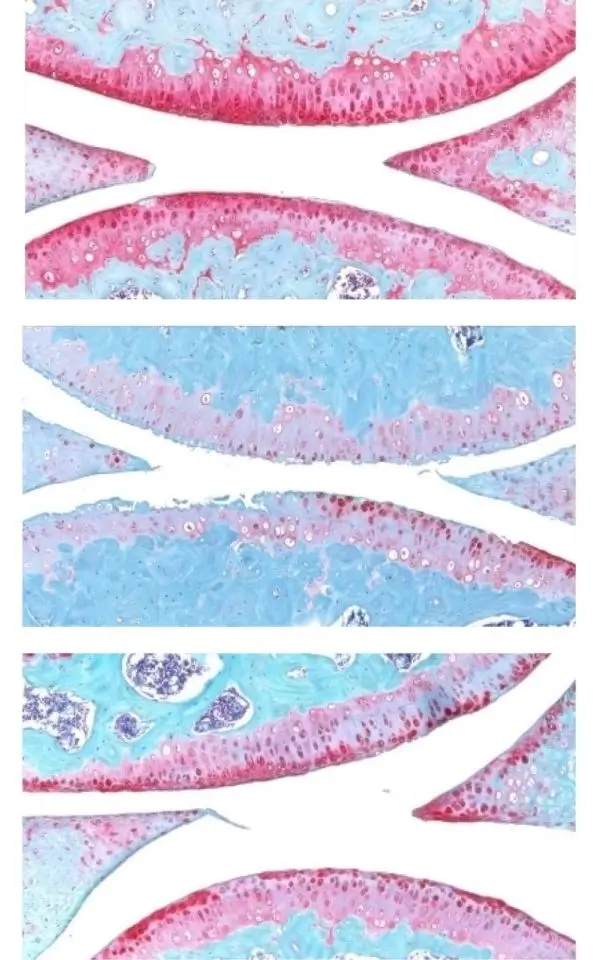

Articulação do joelho de um rato jovem (acima), de um rato idoso (no meio) e de um rato idoso tratado (abaixo). A cor vermelha indica a cartilagem.  Imagem:

Nidhi Bhutani

A inibição da gerozima 15-PGDH leva à regeneração da cartilagem por meio de alterações na expressão gênica e uma mudança na composição celular, de fibrocartilagem para cartilagem hialina. Imagem: Do Artigo: https://www.science.org/doi/10.1126/science.adx6649

Uma análise mais detalhada dos condrócitos nas articulações de camundongos idosos e jovens mostrou que os condrócitos idosos expressavam mais genes prejudiciais envolvidos na inflamação e na conversão da cartilagem hialina em osso indesejado, e menos genes envolvidos no desenvolvimento da cartilagem.

Os pesquisadores também conseguiram identificar subcategorias de condrócitos senescentes que alteram seus padrões de expressão gênica após o tratamento.

Uma delas, que expressa 15-PGDH e genes envolvidos na degradação da cartilagem, teve sua prevalência reduzida de 8% para 3% após o tratamento.

Outra, que não expressa 15-PGDH, mas expressa genes envolvidos na produção de fibrocartilagem, também teve sua prevalência reduzida: de 16% para 8% após o tratamento.

Uma terceira população, que não produz 15-PGDH e que expressa genes envolvidos na formação de cartilagem hialina e na manutenção da matriz extracelular necessária para sua função, teve sua prevalência aumentada de 22% para 42% após o tratamento.